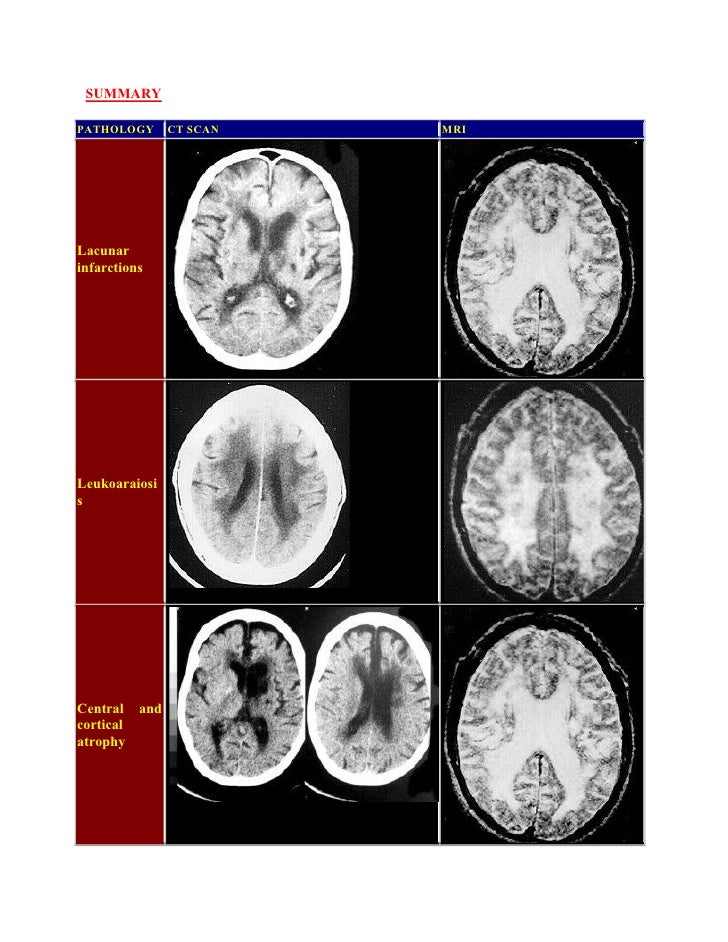

Radiological pathology of microvascular brain disease Can You Reverse Microvascular Disease Web coronary microvascular disease or mvd, sometimes called small artery disease or small vessel disease. The goals of treatment for small vessel disease are to control the narrowing of the small blood. 1 to 1.5 litres of blood go through the brain every minute. Web but sometimes, angina arises from problems in the network of tiny blood vessels in the. Can You Reverse Microvascular Disease.